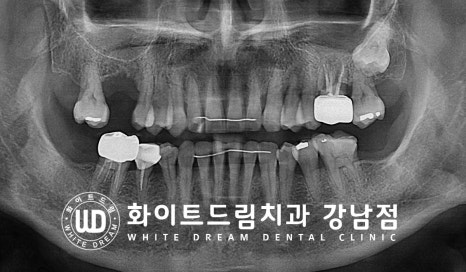

환자분의 최종 치료 후 x-ray 사진입니다.

잇몸뼈의 가장 단단한 부분을 피질골이라고 하는데

상악동을 거상한 부위에 피질골이 잘 형성되어 임플란트를 단단하게 잡아주고

상악동이 정상적으로 회복되었다는 것을 확인할 수 있습니다.

▲ 상악동 거상술을 동반한 상악 어금니 임플란트 치료 전/후

[동일 인물이며 동일 환경에서 촬영됨 / 기간 : 23.04.04 - 23.10.18]